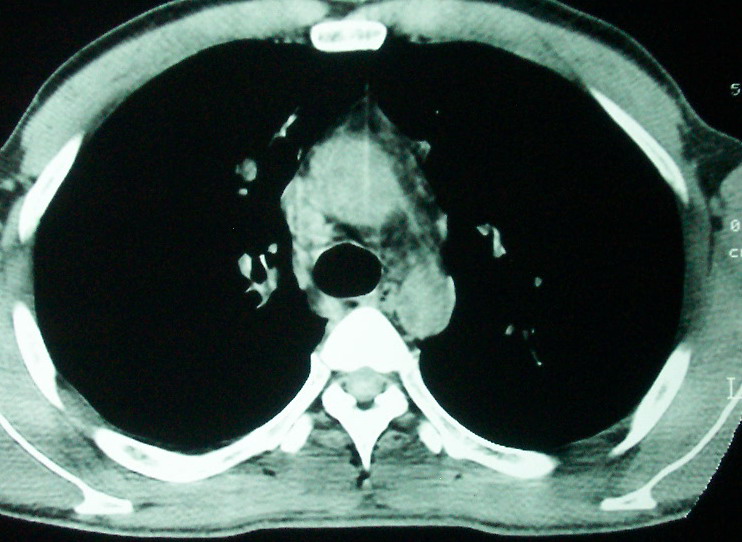

m      37y      发热   咳脓痰月余      ct肺脓肿但住院抗炎治疗后双肺内结节不知该如何解释

治疗后见左肺下野病灶较前缩小但双肺内结节影似无变化请较各位老师该如何下结论    治疗前wbc14.5 治疗后wbc 11.0

1、左下肺鳞癌伴两肺及纵隔淋巴结转移;

2、两上肺支扩伴慢性炎症。

左下肺病灶除了明显的厚壁空洞 气液平外,明显见壁结节,另两肺多发小结节,综合考虑:左下肺周围性肺癌伴肺内转移.

如果你仔细的同层面对比,你会发现所有的病灶均有比较明显的吸收、缩小。病变的形态,特别是脓肿的形态、壁的厚薄、内壁均有很大的变化,均在往好的方面发展。与临床症状、血像均符合,治疗效果比较显著,就是肺脓肿并双肺的化脓性炎症灶。